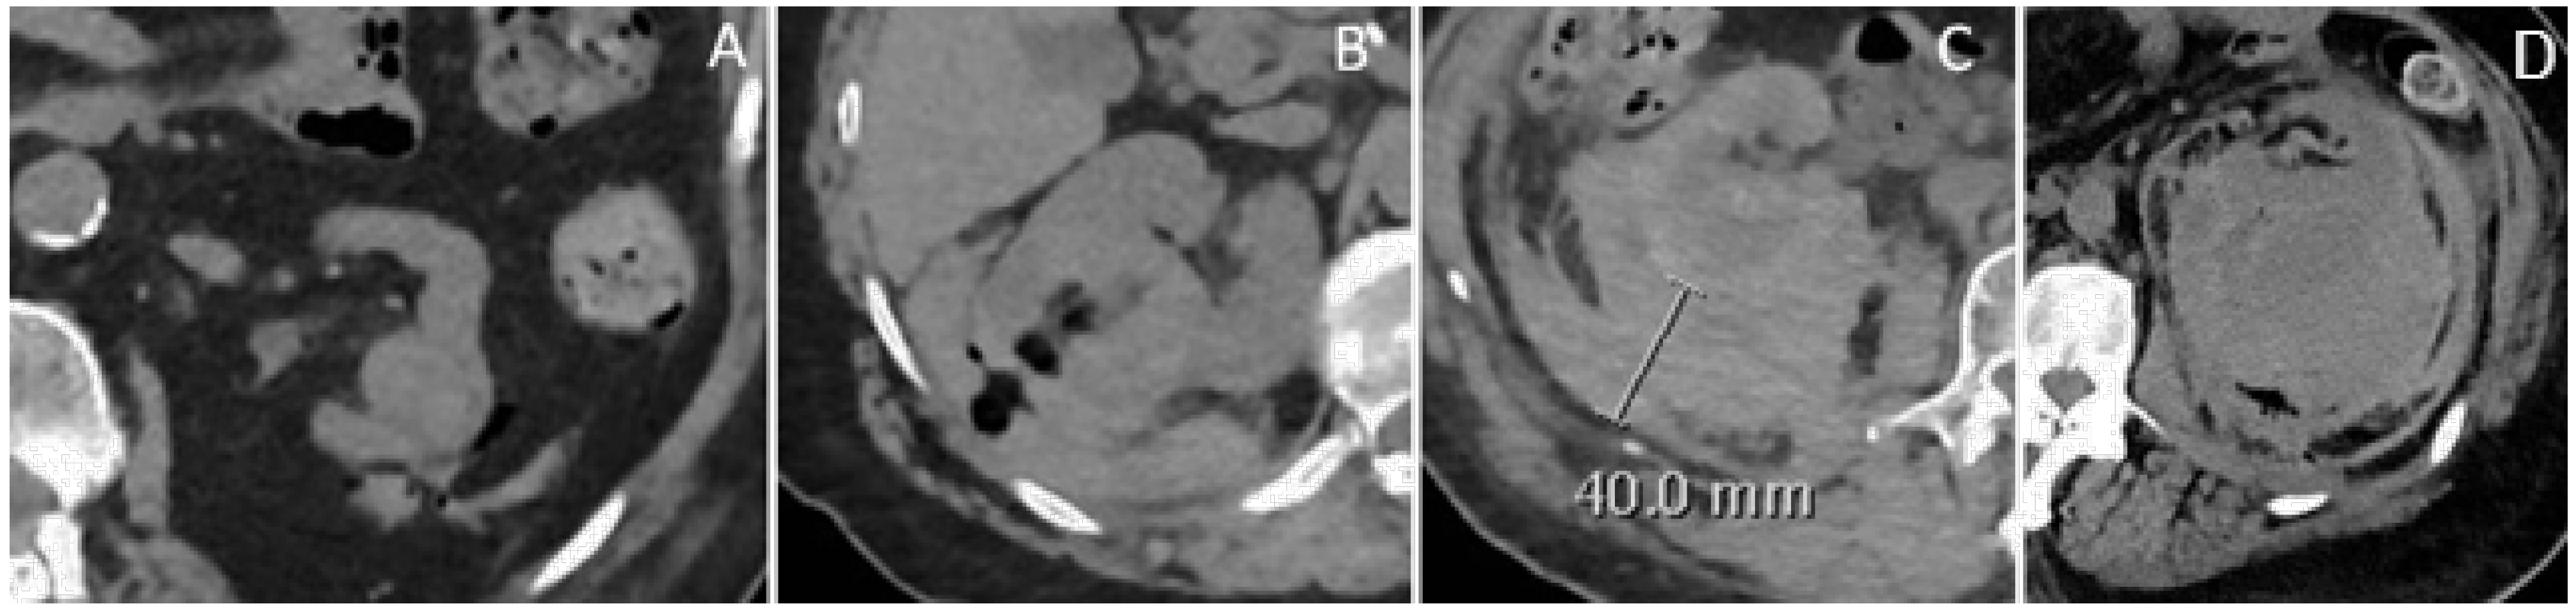

- Patients with mild hemorrhage (small perirenal fluid without an organized hematoma) were discharged with next-day clinical and laboratory evaluation.

- Patients with mild–moderate hemorrhage (hematoma < 3 cm in diameter) were admitted for at least 24 h of observation, with further clinical and laboratory evaluations at 12-h intervals.

- Patients with moderate to severe hemorrhage (hematoma > 3 cm or with extension/contrast extravasation) were promptly evaluated by both a surgeon and the interventional radiologist for further management.

2.6. Classification of Hemorrhagic Complications

- Mild: Minimal perirenal fluid, no organized hematoma.

- Mild–moderate: Hematoma with a maximum transverse diameter < 3 cm.

- Moderate: Hematoma > 3 cm or extension into the retroperitoneum.

- Severe: Extensive hematoma with potential renal capsule rupture and contrast extravasation.